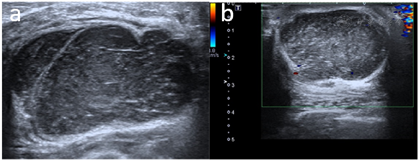

入院后完善检查。超声所见:左乳内见四个低回声结节,大小分别为左19.3 mm×30.1 mm、23.9 mm×44.0 mm、23.7 mm×40.0 mm、31.9 mm×48.9 mm,边界尚清,形态欠规则,内见条索样高回声,后方回声增强,CDFI未见明显血流信号。

超声提示:左乳多发实性肿块(BI-RADS 4a类,建议超声造影)(图1)。